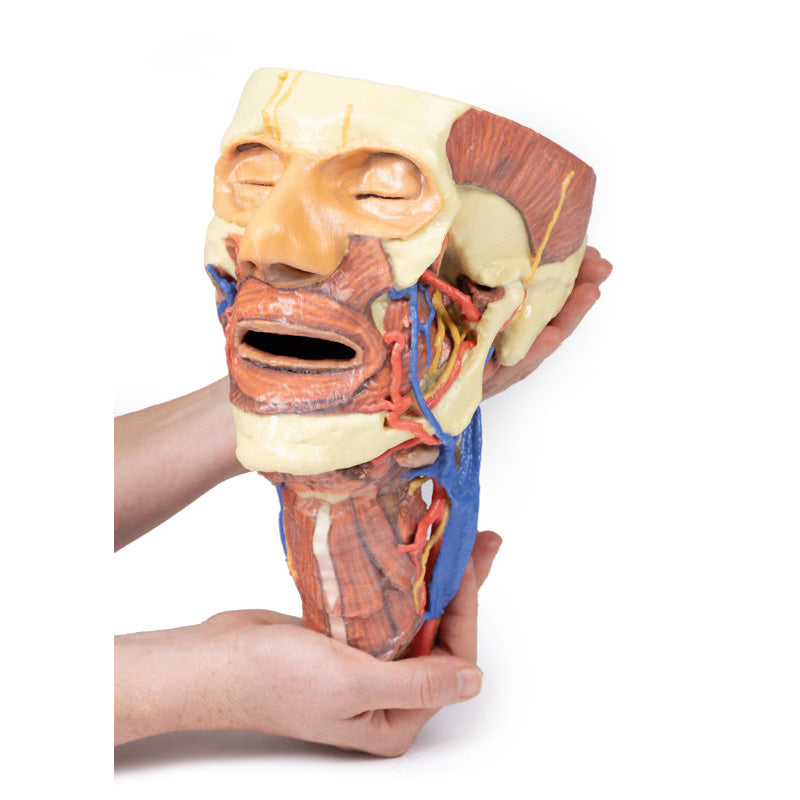

The face: On the right side of the head the parotid gland has been removed to reveal the facial nerve and all its branches (temporal, zygomatic, buccal, marginal mandibular and cervical) and demonstrate the spatial relations of structures embedded in the gland from superficial to deep (facial nerve, retromandibular vein, external carotid artery). In the surrounding region the temporalis, masseter and posterior belly of digastric are exposed, as are and the facial artery, transverse facial artery and superficial temporal artery. The facial vein and transverse facial vein are clearly visible uniting to form the common facial vein which is joined by the retromandibular vein to form the external jugular vein.

Viewed from the anterior aspect the face has been dissected to display some of the facial muscles around the mouth (buccinator [on the left], orbicularis oris and zygomaticus major). On the left side of the infratemporal fossa has been open to expose the medial and lateral pterygoids.

The lateral pterygoid is divided to show the mandibular division of the trigeminal nerve dividing into the lingual nerve and the inferior alveolar branch. Also on the left side the branches of the ophthalmic division of the trigeminal that supply the skin above the eyebrows and scalp (supraorbital [left only] and supratrochlear nerves [both sides]) are dissected. The submandibular gland is clearly visible below the mandible on both sides as are the facial arteries and veins as they course over the mandible.

This 3D print specimen preserves a series of features of the head and visceral column of the neck:The face: On the right side of the head the parotid gland has been removed to reveal the facial nerve and all its branches (temporal, zygomatic, buccal, marginal mandibular and cervical) and demonstrate the spatial relations of structures embedded in the gland from superficial to deep (facial nerve, retromandibular vein, external carotid artery). In the surrounding region the temporalis, masseter and posterior belly of digastric are exposed, as are and the facial artery, transverse facial artery and superficial temporal artery. The facial vein and transverse facial vein are clearly visible uniting to form the common facial vein which is joined by the retromandibular vein to form the external jugular vein.

Viewed from the anterior aspect the face has been dissected to display some of the facial muscles around the mouth (buccinator [on the left], orbicularis oris and zygomaticus major). On the left side of the infratemporal fossa has been open to expose the medial and lateral pterygoids.

The lateral pterygoid is divided to show the mandibular division of the trigeminal nerve dividing into the lingual nerve and the inferior alveolar branch. Also on the left side the branches of the ophthalmic division of the trigeminal that supply the skin above the eyebrows and scalp (supraorbital [left only] and supratrochlear nerves [both sides]) are dissected. The submandibular gland is clearly visible below the mandible on both sides as are the facial arteries and veins as they course over the mandible.